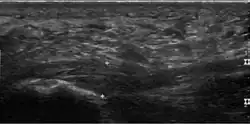

Thickened plantar fascia in ultrasound

Plantar fasciitis is usually diagnosed by a healthcare provider after consideration of a person's presenting history, risk factors, and clinical examination.[4][17][18] Palpation along the inner aspect of the heel bone on the sole may elicit tenderness during the physical examination.[4][11] The foot may have limited dorsiflexion due to excessive tightness of the calf muscles or the Achilles tendon.[7] Dorsiflexion of the foot may elicit the pain due to stretching of the plantar fascia with this motion.[4][12] Diagnostic imaging studies are not usually needed to diagnose plantar fasciitis.[7] Occasionally, a physician may decide imaging studies (such as X-rays, diagnostic ultrasound, or MRI) are warranted to rule out serious causes of foot pain.

The plantar fascia has three fascicles-the central fascicle being the thickest at 4 mm, the lateral fascicle at 2 mm, and the medial less than a millimeter thick.[19] In theory, plantar fasciitis becomes more likely as the plantar fascia's thickness at the calcaneal insertion increases. A thickness of more than 4.5 mm ultrasound and 4 mm on MRI are useful for diagnosis.[20] Other imaging findings, such as thickening of the plantar aponeurosis, are nonspecific and have limited usefulness in diagnosing plantar fasciitis.[13]